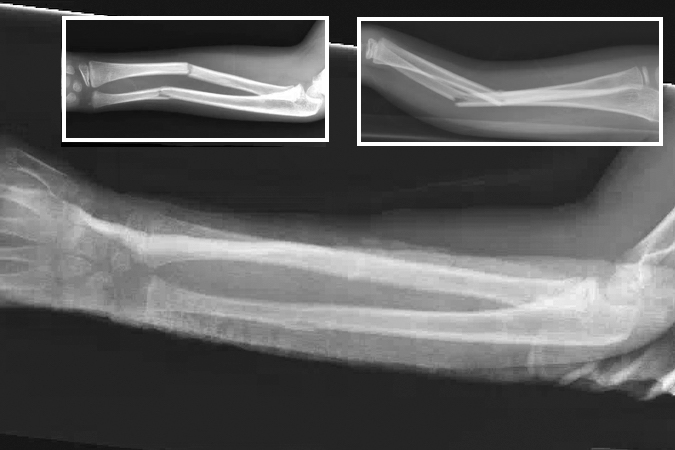

Galeazzi fracture

- Also known as a reverse Monteggia fracture or Piedmont fracture, the Galeazzi fracture is fracture of the middle to distal third of the radial shaft combined with a subluxation or dislocation of the distal radioulnar joint (DRUJ).12,13

- The Galeazzi fracture is considered a true forearm axis injury because of concomitant bone and soft tissue injuries. The triangular fibrocartilage complex (TFCC) and/or interosseous membrane (IOM are particularly at risk and their injury can contribute to forearm instability.12,14

- These injuries typically result from direct impact to the radius with forearm pronation. When a patient sustains a radial shaft fracture in the middle to distal third of the bone, the possibility of an associated DRUJ injury should be investigated.12,14

- Galeazzi fractures are more common in pediatric patients than adults. In children and adolescents, they are usually caused by sports injuries, falls from a height, or motor vehicle accidents.11,13

Imaging13

- Radiology studies - X-ray

- Anteroposterior (AP) and lateral views are usually sufficient, but an oblique view may help to better classify the injury and define a fracture line that is present but not apparent on the AP and lateral views.

- Because a coexistent joint injury is always possible, the distal wrist joint and elbow joint should always be included on the forearm X-rays or X-ray separately.